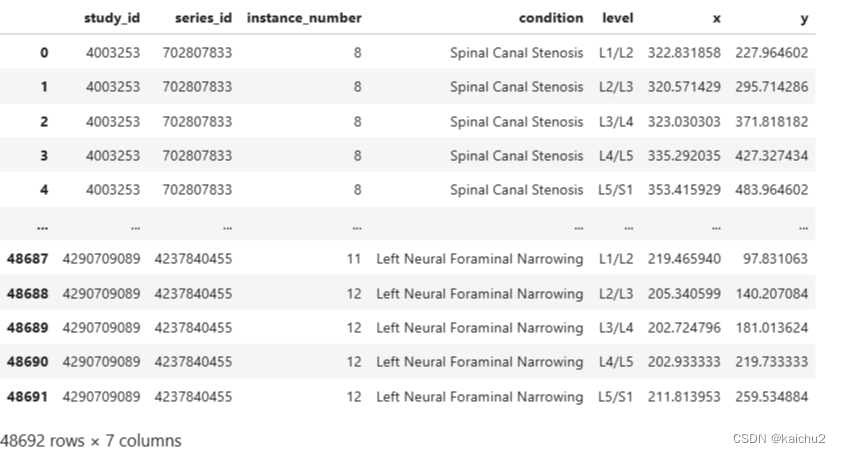

2.3、train_label_coordinates说明

study_id:研究编号,表示不同的医学研究项目或对象的唯一标识。

series_id:系列编号,通常指的是特定研究编号下的一系列相关检查或数据集的标识。

instance_number:实例编号,可能表示单个被试或对象在特定系列中的编号。

condition:条件,描述了进行医学检查时的具体条件或病理状态,如“Spinal Canal Stenosis”指的是“椎管狭窄”。

level:水平,可能表示检查的具体部位或水平,如“L1/L2”表示腰椎的第一和第二椎骨之间。

X:X轴坐标值,可能表示在某种检查(如影像学检查)中标记点或感兴趣区域的X轴坐标。

y:Y轴坐标值,与X轴坐标类似,表示标记点或感兴趣区域的Y轴坐标。

例如,第一行记录了一个研究编号为4003253,系列编号为702807833的实例,在“Spinal Canal Stenosis”(椎管狭窄)条件,“L1/L2”水平下的X、Y坐标值分别为322.831858和227.964602。

其中condition就是对应train中的五个分类标签,level对应上面的五个椎间盘水平;